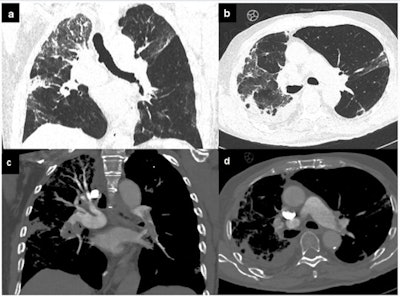

While bedside echocardiography remains a first-line and ease-of-use diagnostic tool, appropriate use of second-line techniques, such as cardiac CT and cardiovascular MRI, allows the reliable exclusion of coronary artery disease together with the characterization of underlying pathological substrate.

"A progressive shift from acute to chronic cardiovascular damage is not uncommon, even in apparently healed patients, and includes conditions like chronic thromboembolic pulmonary hypertension, recurrent arrhythmias, and progression to dilated cardiomyopathy. Accordingly, careful follow-up of these patients should be ordered in the convalescent stage," the authors recommended.

Pericarditis is not a common complication in COVID-19, but it should be promptly considered in patients with chest pain, ST elevation on electrocardiogram, and a normal coronary angiogram. A misdiagnosis can produce life-threatening consequences, such as cardiac tamponade.

Despite the fact that CT and cardiac MRI are not included in the diagnostic criteria for pericarditis, these imaging modalities can provide supportive findings and are strongly recommended as second-level testing for diagnostic workup of the pathology, according to the authors. The hallmark of cardiac MRI in acute pericarditis includes the combination of diffusely edematous and enhancing pericardial layers with a variable amount of effusion, as shown in the figure below. MRI may serve not only to confirm the diagnosis but also to rule out alternative overlapped diagnoses such as myocarditis or pulmonary embolism.